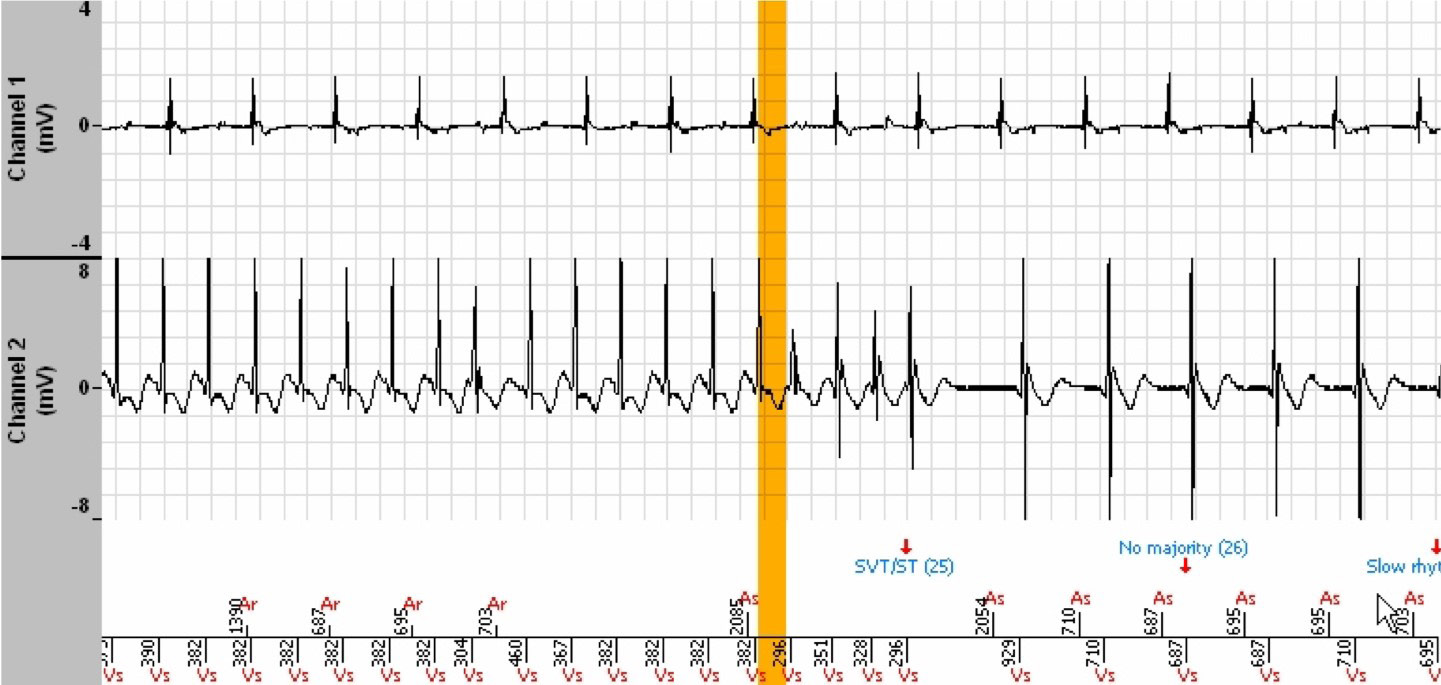

- In this EGM, it is indisputably a conducted AF with irregular ventricular rhythm, appropriately diagnosed as SVT.

- In this other EGM, of another episode labelled Slow VT, the tachycardia is perfectly stable, monomorphic and of very different morphology compared to the ventriculograms of the conducted AF.

- Evidence that this latter EGM does indeed show ventricular tachycardia lies in the observation of the continuation of this tachycardia whereas the AF has terminated spontaneously.

- When the ventricular tachycardia terminates, we find the conducted PR sinus rhythm combination. Note the morphology of the QRS in sinus rhythm which corresponds to that of the conducted AF cycles, and to that of the 11 cycles that follow the orange bar of the EGM of our clinical case. Those cycles which precede the orange bar and those that follow the ATP have a different morphology (less amplitude), which evokes a VT. The morphology of this VT is also different from the obvious VT of the episode shown above.

- The interpretation of the tracing of this clinical case is thus the following (subject to discussion): The tachycardia is a Slow VT which terminates, followed by ventricular cycles conducted by the AF which enter the VT zone, completing the persistence

initiated well before, and induce an ATP which results in the return of the Slow VT. This Slow VT is different from that of another episode, revealed by the two EGMs above.